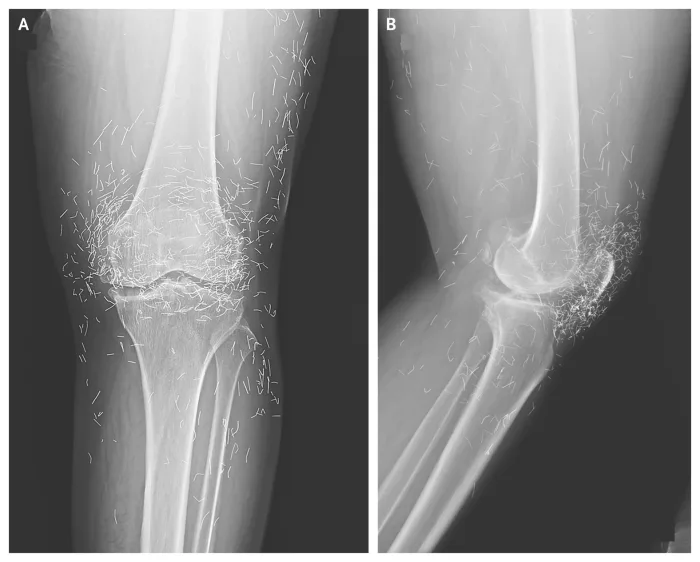

A routine X-ray revealed an unexpected surprise when doctors examined the knees of a 65-year-old woman suffering from severe joint pain. What they found was nothing short of astonishing — hundreds of tiny gold needles embedded deep in her tissue.

A X-ray of the patient’s knee showing acupuncture needles embedded in the tissue, Photo Credit: Reddit

Acupuncture, a traditional therapy widely used in Asia, involves inserting thin needles into specific points on the body in an effort to relieve pain or treat illness. In this case, however, doctors say the gold needles were left behind intentionally as part of her treatment plan, designed to deliver continuous stimulation to the affected area.

There are other complications as well. Needles lodged in tissue can interfere with medical imaging. “They can obscure parts of the anatomy on an X-ray,” Guermazi noted. Even more alarming, patients with metal fragments in their bodies should never undergo an MRI, as the magnetic force could cause the needles to move — potentially puncturing blood vessels and causing life-threatening damage.